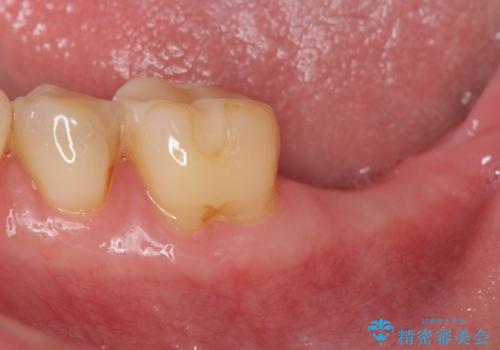

- 「歯から異臭がする。」とのことで相談に来院されました。

X線検査を行ったところ、セラミッククラウン下に虫歯が再発し、歯の破折も認めました。

歯の抜去を行い、骨の造成を含めたインプラントによる咬合機能の回復を図ります。